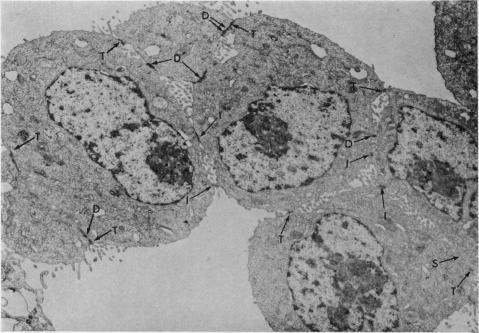

To analyse the effect of ethylenediamine tetraacetate (EDTA) on tumour cell adhesiveness, fine structure of intercellular junctions of rat ascites hepatoma cells AH136B and AH7974 (both forming cell islands in vivo) was first compared. The close contact of the apical portion of both cell islands was composed of tight junctions with a narrow gap. The close contact of the inner portion of AH136B cell islands was largely by simple apposition, while that of AH7974 cell islands had many intermediate junctions and desmosomes. Treatment with EDTA (2 mM) induced morphological alteration of simple apposition, intermediate junctions and desmosomes, but tight junctions remained intact. The effect of EDTA on such junctional complexes seemed to be partially reversible on readministration of Ca ions. Changes in desmosomes, as confirmed on AH7974 cells, were initiated by disappearance of the central disc of electron-dense materials, followed by marked opening of intercellular space and disappearance of endoplasmic laminar plaque. These results suggest that Ca ions may be concerned with maintaining the integrity of junctional complexes other than tight junctions.

为分析乙二胺四乙酸(EDTA)对肿瘤细胞黏附性的影响,首先比较了大鼠腹水肝癌细胞AH136B和AH7974(两者在体内均形成细胞岛)细胞间连接的精细结构。两个细胞岛顶端部分的紧密接触由间隙狭窄的紧密连接组成。AH136B细胞岛内部分的紧密接触主要是简单并置,而AH7974细胞岛的紧密接触有许多中间连接和桥粒。用EDTA(2 mM)处理可诱导简单并置、中间连接和桥粒的形态改变,但紧密连接保持完整。再次给予钙离子后,EDTA对这种连接复合体的作用似乎部分可逆。在AH7974细胞上证实,桥粒的变化始于电子致密物质中央盘的消失,随后细胞间隙明显增宽,内质层板消失。这些结果表明,钙离子可能与维持除紧密连接之外的连接复合体的完整性有关。